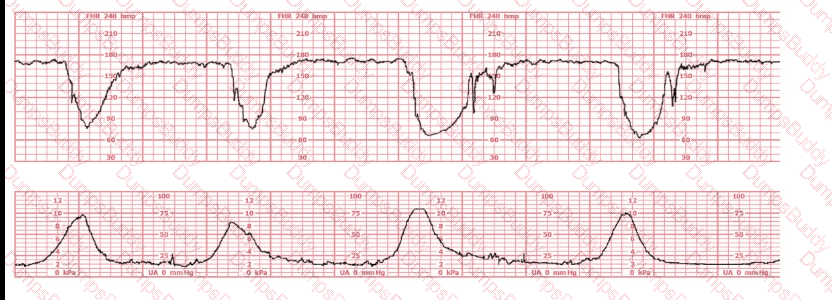

The decelerations seen in the fetal monitoring tracing shown are best described as: